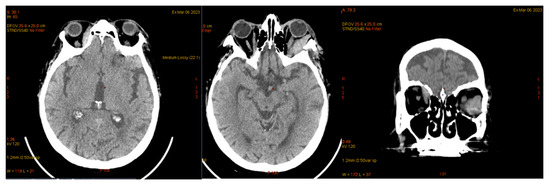

| January 2023 | second extramedullary relapse bilateral ocular left eye clinically, imaging, and biopsy demonstrated right eye demonstrated by imaging | methotrexate, asparaginase, calcium folinate radiotherapy, 30 gy/15 sessions result: imaging complete remission |